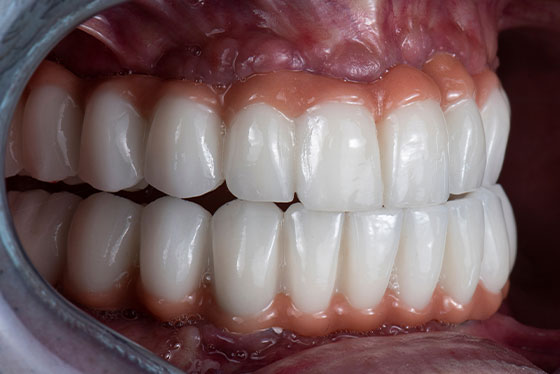

All-on-4では、インプラントで固定された土台の上に歯を装着するため、入れ歯のように外れてしまう心配が少なく、おしゃべりやお食事も、より自然に楽しめます。

山下歯科医院では、噛み合わせや見た目も、お一人おひとりのお口に合わせて丁寧に調整していきます。

All-on-4では、上下それぞれの顎に12本の歯が入ります。上下ともに治療を行う場合、症例によっては、手術当日からすべての歯が入り、噛める状態を目指すことも可能です。